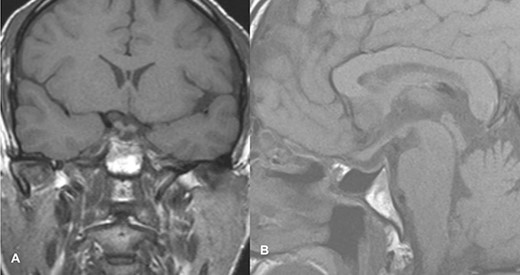

MRI imaging showed a 2 × 1.6 × 1.6 cm sized sellar lesion arising from the pituitary fossa with an intrinsic high T1 signal in the periphery, extending superiorly in the suprasellar region and laterally, causing a mass effect on the left cavernous sinus. A signal void was seen in T2-weighted images suggestive of hemorrhage (Fig. 3).

MRI images of post-contrast sagittal T1 (A), sagittal T1 (B), axial T2 (C), and post-contrast axial T1-weighted images (D) showing a 2 cm × 1.6 cm × 1.6 cm sized sellar lesion arising from the pituitary fossa extending superiorly in the suprasellar region and laterally causing a mass effect on the left cavernous sinus with intrinsic high T1 signal in the periphery and signal void on T2-weighted images suggestive of hemorrhage.